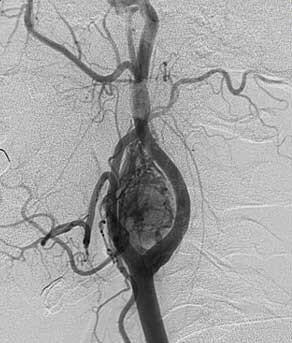

Каротидная хемодектома — это новообразование, произрастающее из ткани каротидного синуса (нейроэндокринная ткань АПУД-системы). Локализуется в области передней поверхности шеи — там, где происходит бифуркация сонной артерии